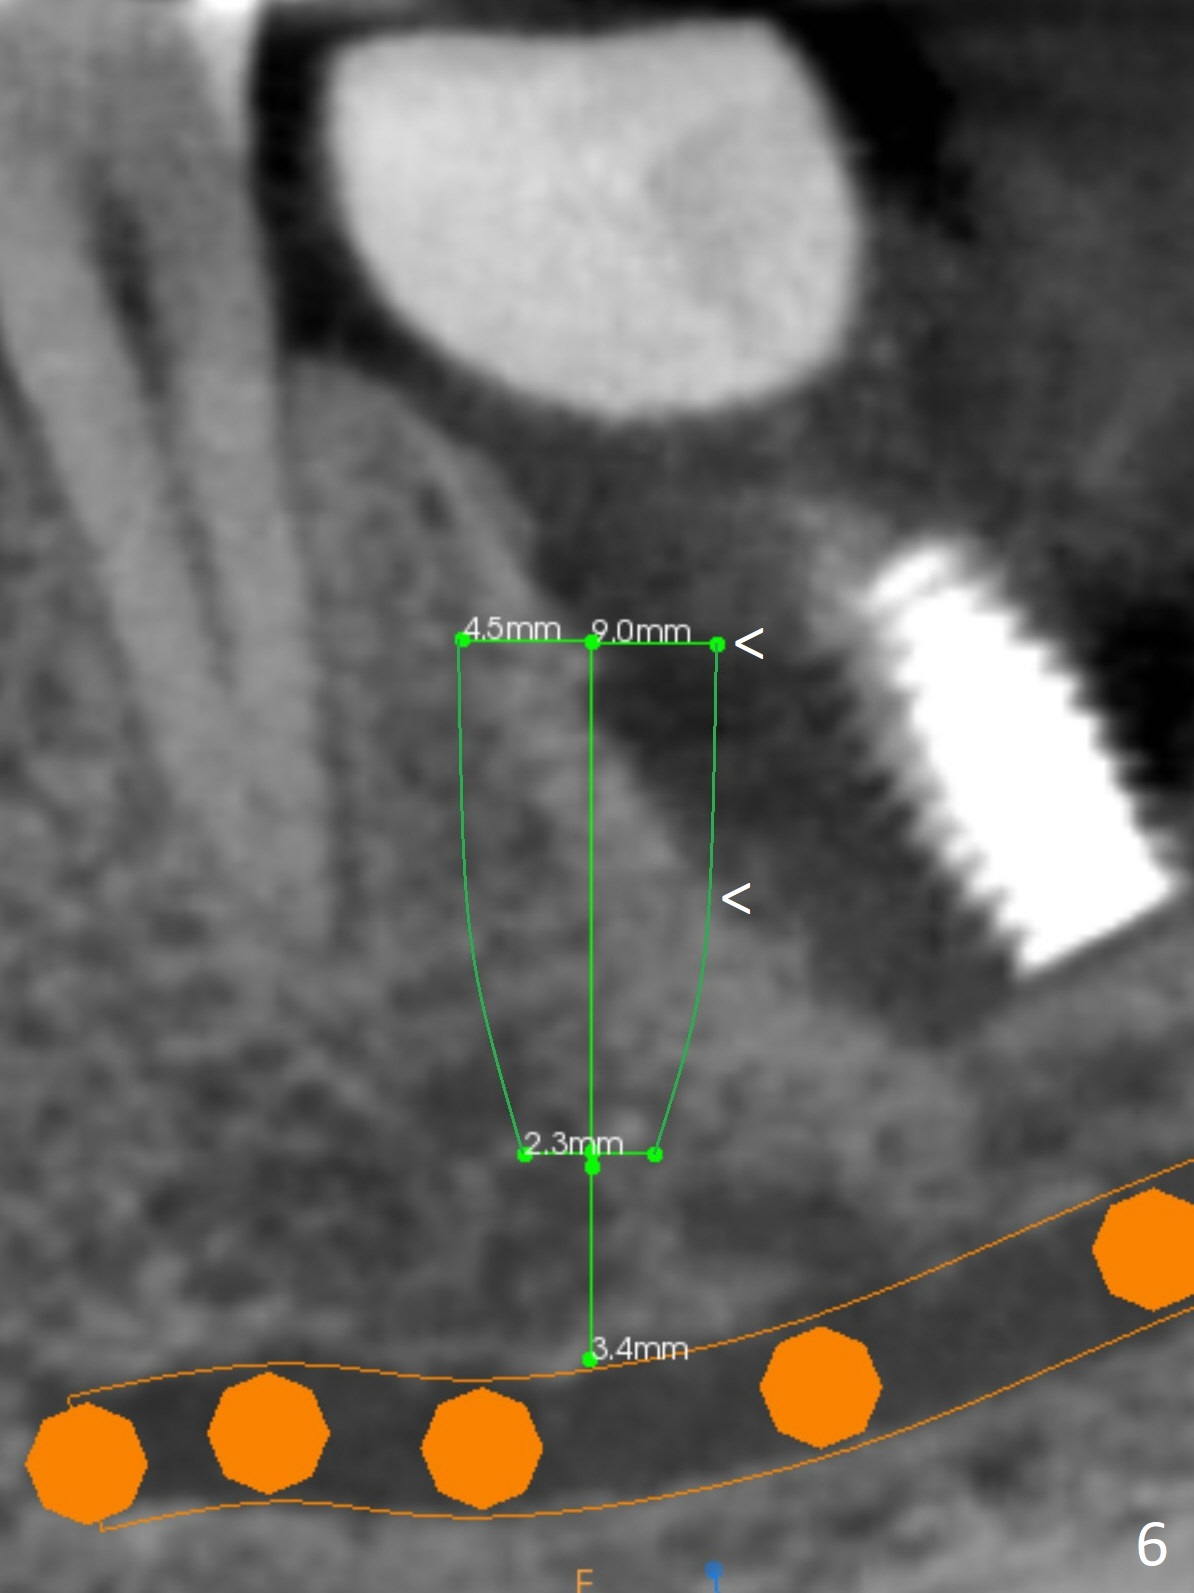

When the patient returns for treatment, the implant at #19 is mobile with tenderness (without purulence, Fig.1). She finally agrees to have CT taken (Fig.2,3 (coronal section (L: lingual))). The implant is removed after several carpules of cocktail anesthetics for infiltration and one carpule for block. Osteotomy is initiated in the mesial slope of the defect (Fig.2,4). The advantage of immediate implant re-placement is wide bone at the intended area (Fig.3). After change in trajectory (compare Fig.4 (4x11 mm dummy implant) and Fig.5), a 4.5x9 mm IBS implant is placed with insertion torque of 50 Ncm (Fig.5); with Osteogen plug placed in the distal defect, allograft (*) is placed immediately distal to the implant. With the longest cuff available (4 mm), the margin of the abutment (4.5x4(4) mm) is equi-crestal (>). When the 9 mm long implant is placed deep, the coronal threads of the implant are distally exposed (Fig.6 between arrowheads) less than those of the 11 mm one placed superficial (Fig.2). Intraoperative socket hemorrhage is controlled by packing gauze saturated with Epinephrine 1:50,000. The patient chooses not to take Medrol Dose Pack for postoperative edema. She removes periodontal dressing herself prematurely. The socket wound dehiscence is noted the first postop visit (7th day). Fig.7 is taken 9 days postop before re-suturing. The patient insists on removing the implant with dull pain. Three months 10 days postop, she returns with loss of the abutment and a fistula (Fig.8). In fact there is bone formation distal to the implant. Torque wrench has to used to remove the implant.